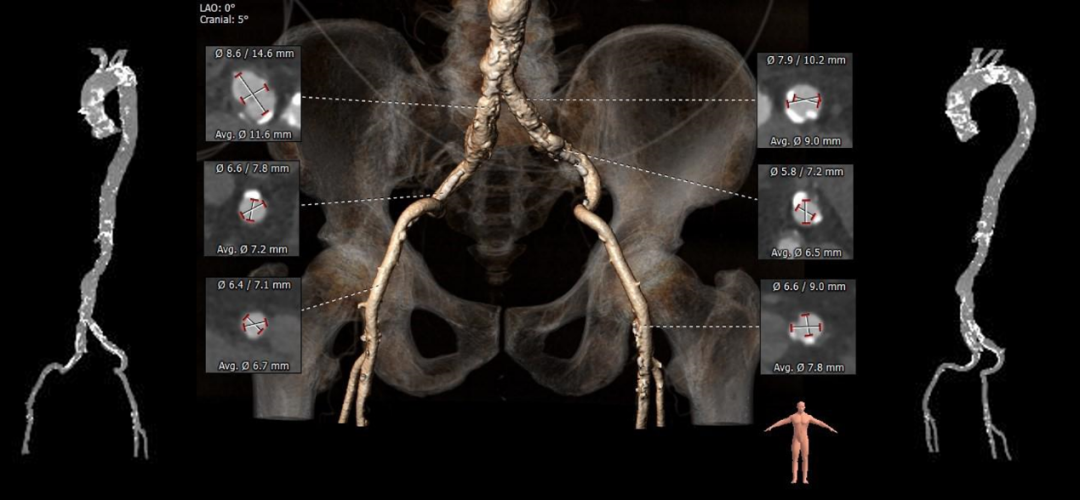

主动脉根部测量

CT特点:三叶式主动脉瓣,瓣叶重度钙化,钙化分布稍欠均匀,主要分布在瓣叶边缘及管壁附着缘,左冠瓣叶窦底长钙化延伸至LVOT;瓦氏窦不大,窦管交界、升主动脉内径偏小,左右冠脉开口高度可,左冠瓣叶稍长,冠脉多发钙化;升主、主动脉弓管壁多发钙化,双侧股髂动脉轻度扭曲,多发钙化,腹主动脉及髂动脉可见瘤样扩张。

瓣上测量

瓣上测量:瓣叶重度钙化,钙化分布稍欠均匀,钙化主要分布在瓣叶边缘,锚定力量主要来源于瓣上2-8mm。

弓部及入路评估

入路血管:双侧股髂动脉轻度扭曲,多发钙化,双侧入路血管直径可,腹主动脉及髂动脉可见瘤样扩张。